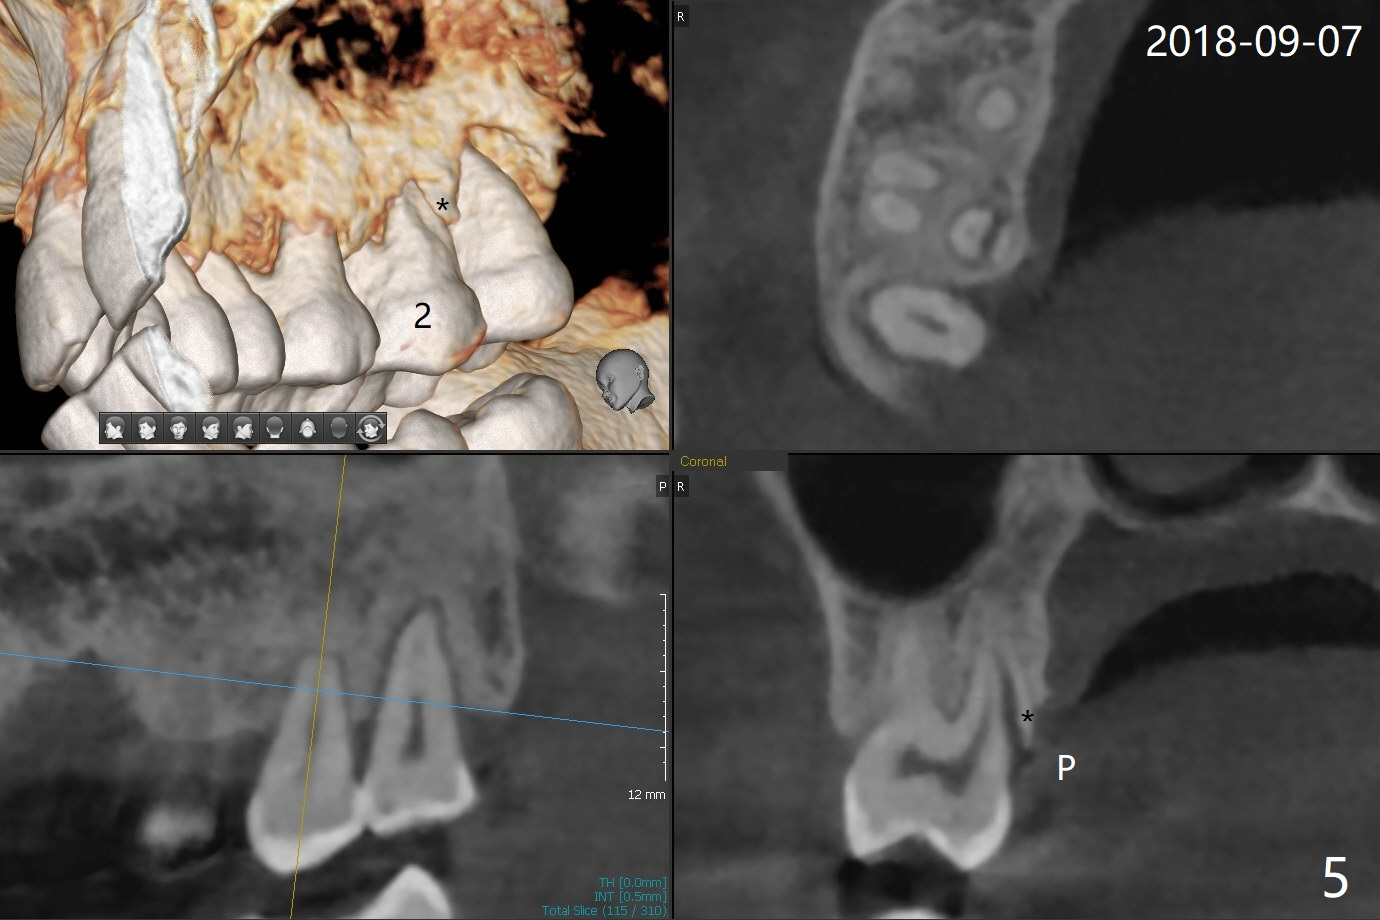

A 56-year-old woman returns to clinic with chief complaint of upper right discomfort (Fig.1) 9 months post #15 implant placement. Clinical exam does not reveal significant finding (periradicular radiolucency (PRRL) at #1 (*) is neglected). Six months later, PRRL at #1 is enlarged (Fig.2 *) with palatal gingival recession, pockets and BOP. The tooth is extracted; its palatal plate is lost, which is consistent with CT taken ~ 1 year earlier (Fig.3). Moreover, the palatal root is incidentally found to be have fractured at #2 (Fig.3,5 *), in the same manner as the tooth #15. Bone loss and root fracture are related to bruxism. Since the tooth #32 is present, an immediate implant could have been placed at #1 (Fig.4).